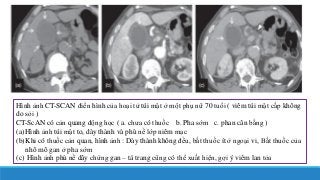

Hình ảnh CT-SCAN điển hình của hoại tử túi mật ở một phụ nữ 70 tuổi ( viêm túi mật cấp không

do sỏi )

CT-ScAN có cản quang động học ( a. chưa có thuốc b. Pha sớm c. phan cân bằng )

(a)Hình ảnh túi mật to, dày thành và phù nề lớp niêm mạc

(b)Khi có thuốc cản quan, hình ảnh : Dày thành không đều, bắt thuốc ít ở ngoại vi, Bắt thuốc của

nhô mô gan ở pha sớm

(c) Hình ảnh phù nề dây chừng gan – tá trang cũng có thể xuất hiện, gợi ý viêm lan tỏa